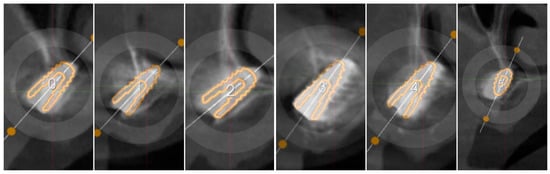

3.1. Alignment Accuracy

3.2. Surgical Guide Accuracy